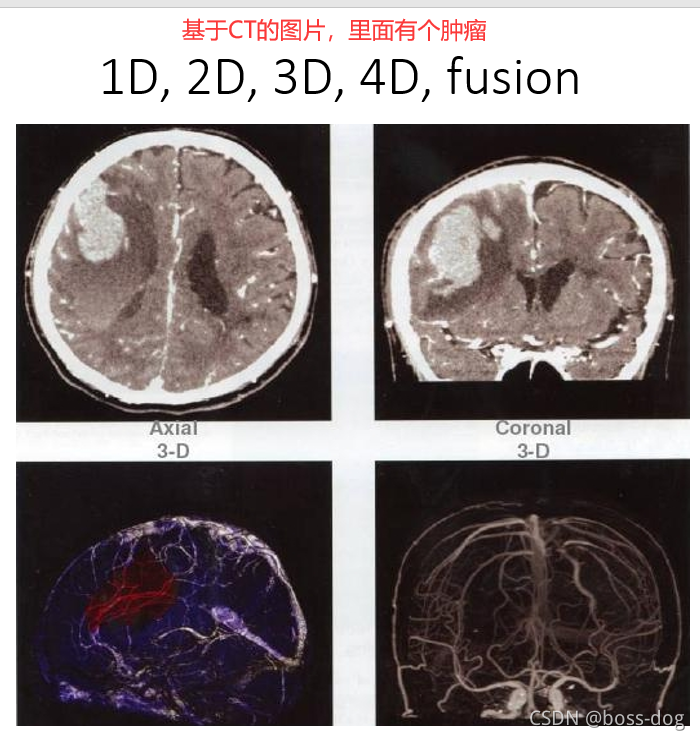

图片的类型

-

一维1D:比如抽血中的各项数指标、血压的数值等等、二维2D:比如心电图采集的图片记录下来的信息、DICOM图片等等、三维3D和四维4D的涉及一些动态图片比如后处理很酷炫的图片或分割的结果等等

上图中将两个图像进行一定的融合,左边PET的图像能够把肿瘤的位置给刻画出来,而CT能够把解剖的如人的骨头、肾、肝显示出来,两个图像进行修正和融合就可以看出来肿瘤到底在哪个位置,进行精准定位。